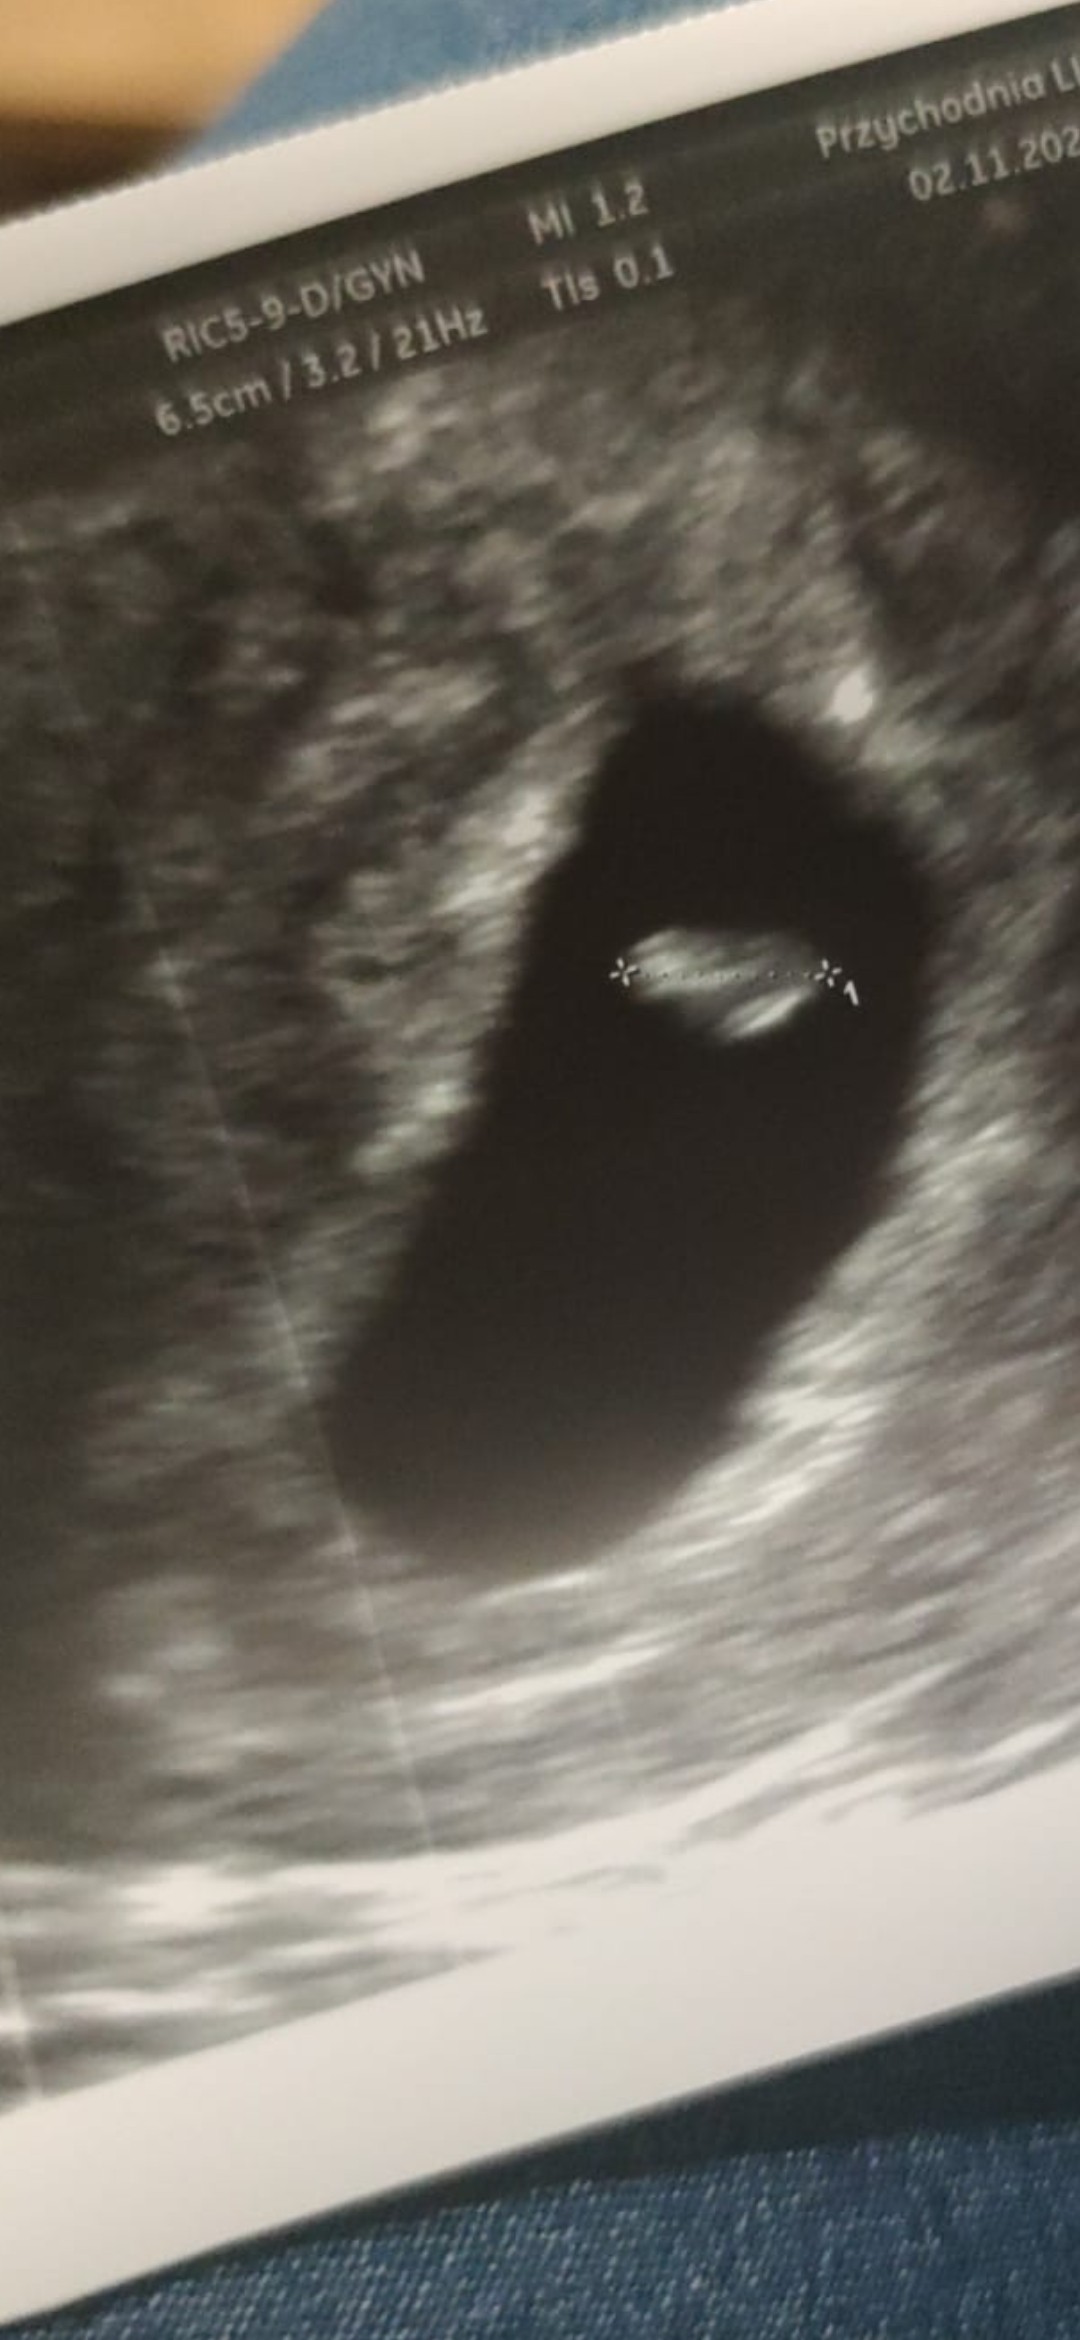

No to dzisiaj same dobre wieści [emoji5] mój dzidziulek ma całe 4,7mm [emoji85][emoji16] i bije już serduszko [emoji3059]

No też wydawało mi się to dziwne 🙄 ale już trudno. I tak cały czas żyłam w przeświadczeniu że mój lekarz ma dobry sprzęt itd ale jak tak patrzę na zdjęcia innych to na moim nawet nie widać gdzie jest pęcherzyk żółtkowy 🙄 tzn domyślam się gdzie może być 😁

Załączniki

• Screenshot_2021-11-02-18-49-32-992_com.whatsapp.jpg

Screenshot_2021-11-02-18-49-32-992_com.whatsapp.jpg

222,6 KB · Wyświetleń: 85